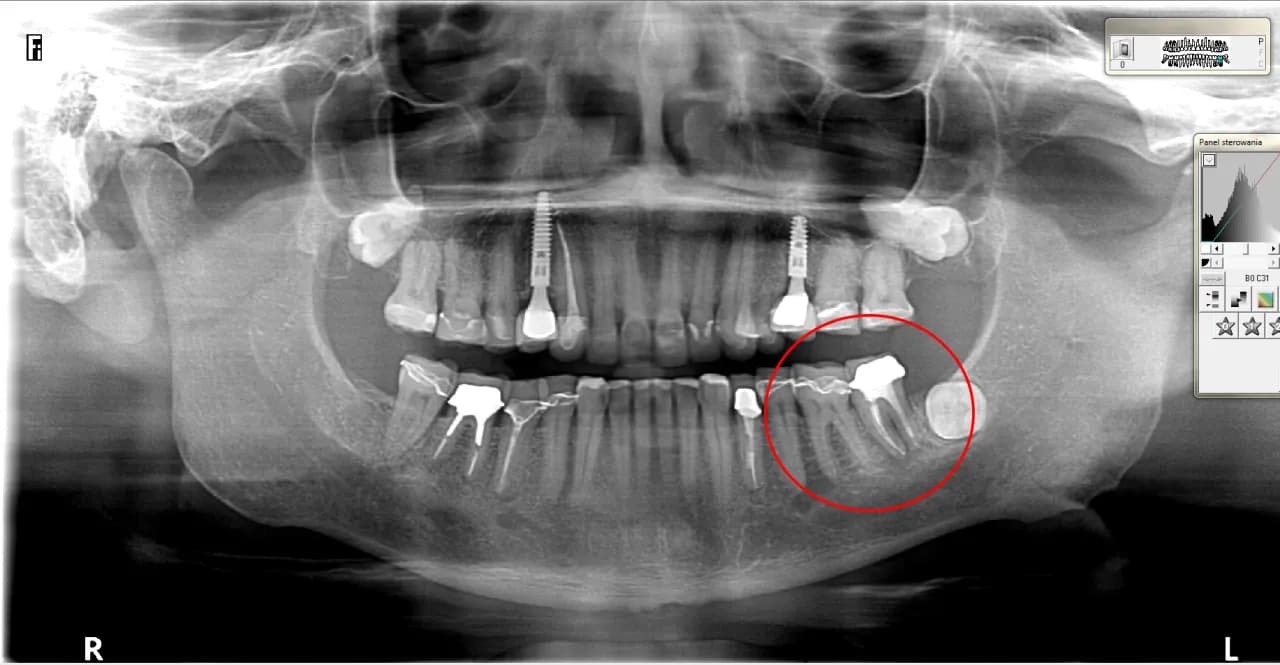

Zdjęcia RTG odgrywają kluczową rolę w diagnozowaniu pionowego pęknięcia korzenia zęba. Dzięki nim dentyści mogą dokładnie ocenić stan zęba oraz otaczających go tkanek. Na zdjęciach RTG specjaliści szukają charakterystycznych oznak, takich jak asymetryczne przejaśnienia w kształcie litery „J” wokół korzenia, które mogą wskazywać na obecność pęknięcia. Te obrazy są niezbędne do postawienia właściwej diagnozy i zaplanowania dalszego leczenia.

W przypadku podejrzenia pęknięcia, zdjęcia RTG mogą ujawnić również inne zmiany, takie jak obecność przetok czy stanu zapalnego w okolicy korzenia. Wczesne wykrycie tych problemów jest kluczowe, ponieważ pozwala na szybsze podjęcie odpowiednich działań terapeutycznych. Dzięki nowoczesnym technologiom, takim jak tomografia komputerowa, diagnostyka staje się jeszcze bardziej precyzyjna, co zwiększa szanse na skuteczne leczenie.